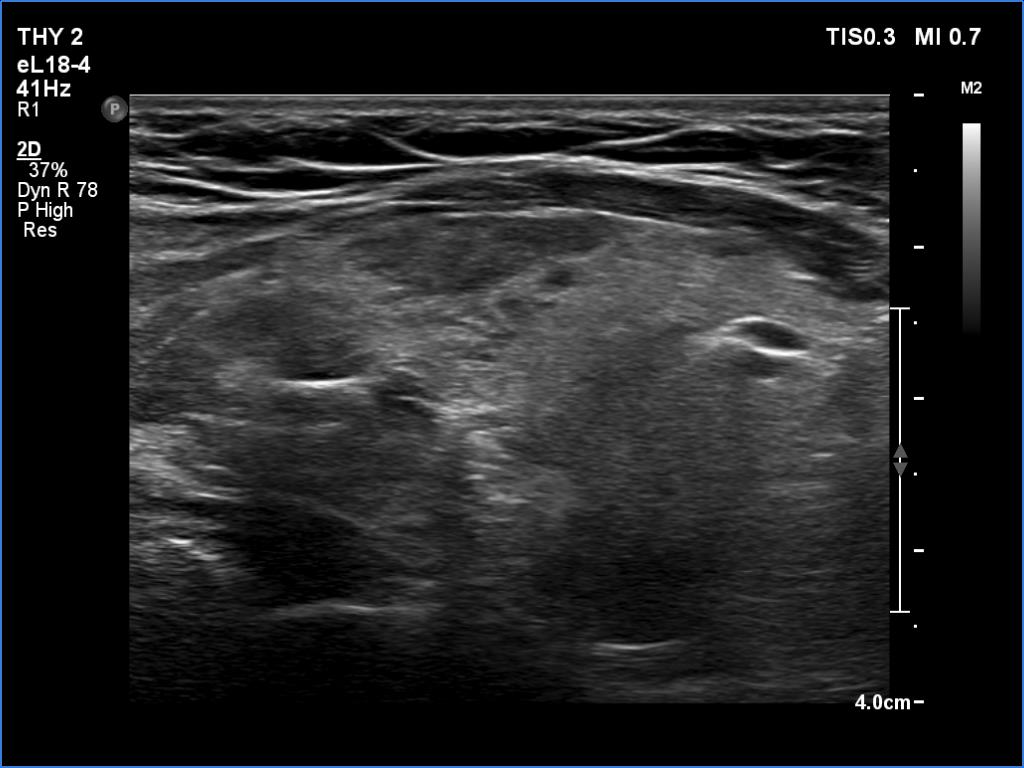

Ultrasonography. The thyroid was echonormal and presented several minimally-moderately hypoechoic areas. One of them, which was located in the central part of the right lobe was deeply hypoechoic and corresponded to pathological nodule. The other lesions seemed to be not true nodules but more active foci of thyroiditis.

Comment. It is worth comparing the deeply hypoechoic nodule with the other discrete lesions. The former has regular, sharp borders, and its echogenicity differs from other areas of the thyroid. These are the main clues of differentiation of a true nodule from a discrete lesion of Hashimoto's thyroiditis.